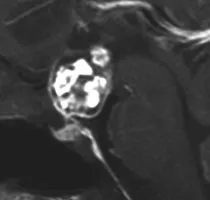

在寻找施罗德教授后,该患者向他叙述了自己的病史。他出现的主要症状包括疲劳、性能下降和勃起功能障碍,双颞侧偏盲。对于颅咽管瘤,磁共振成像(MRI)是首选的检查方法。该患者的MRI显示鞍上颅咽管瘤,肿瘤侵入第三脑室。内分泌检查显示垂体功能部分不足。

使用对比剂的T1加权矢状和冠状MRI图像显示鞍上和室内的颅咽管瘤(双颞侧偏盲)